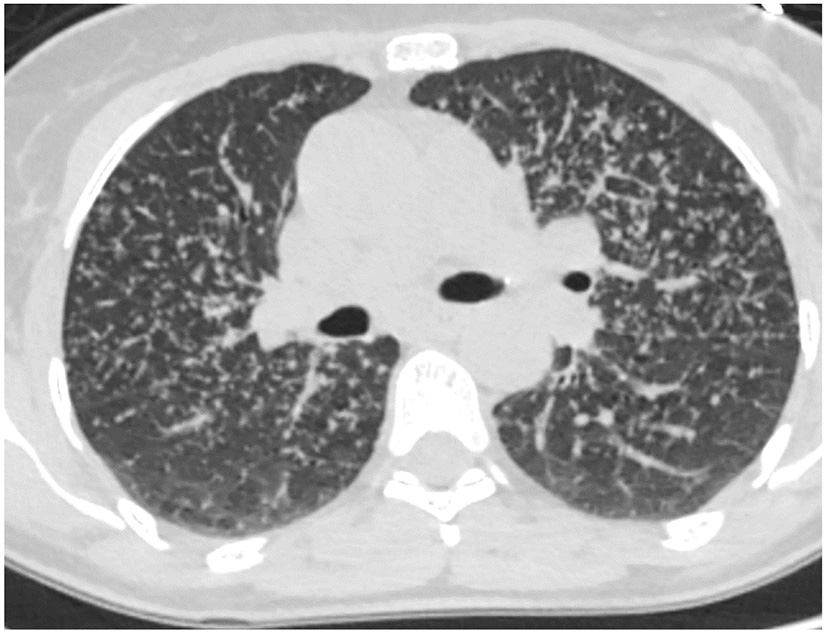

Not all patients who progress with IPF increase their extent of disease. Some progress by changing from a probable UIP to a UIP pattern with the development of honeycombing (Figure 1). Previously we reviewed 103 patients with a working diagnosis of IPF, 68 had a probable UIP pattern on the initial CT, 47% progressed to a UIP pattern with honeycombing (HC) over 51 months, therefore having a progressive phenotype. Thirty five patients had HC on the initial CT scan of which 57% increased the extent of disease over 31 months, also progressive disease. Enlarged pulmonary artery and emphysema were associated with disease progression (22). Serial imaging is used to evaluate progression which is not necessarily discovered between the first and second HRCT scans. Serial CT scans have the added benefit of the early identification of lung cancer (23).

Figure 1

Change from probable UIP pattern to UIP pattern indicative of progressive fibrosis.